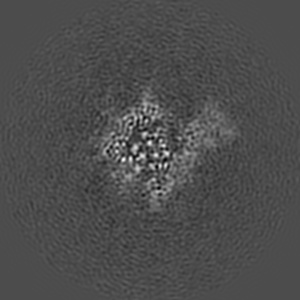

SARS-CoV2 Spike Protein structure at pH 7.4 with C1 Symmetry (Class 8)